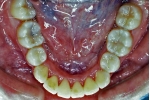

| 初診時